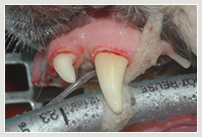

Parodontalerkrankung hochgradig! Extraktion der hochgradig

erkrankten Zähne

Parodontalerkrankung hochgradig

(mit Sonde)